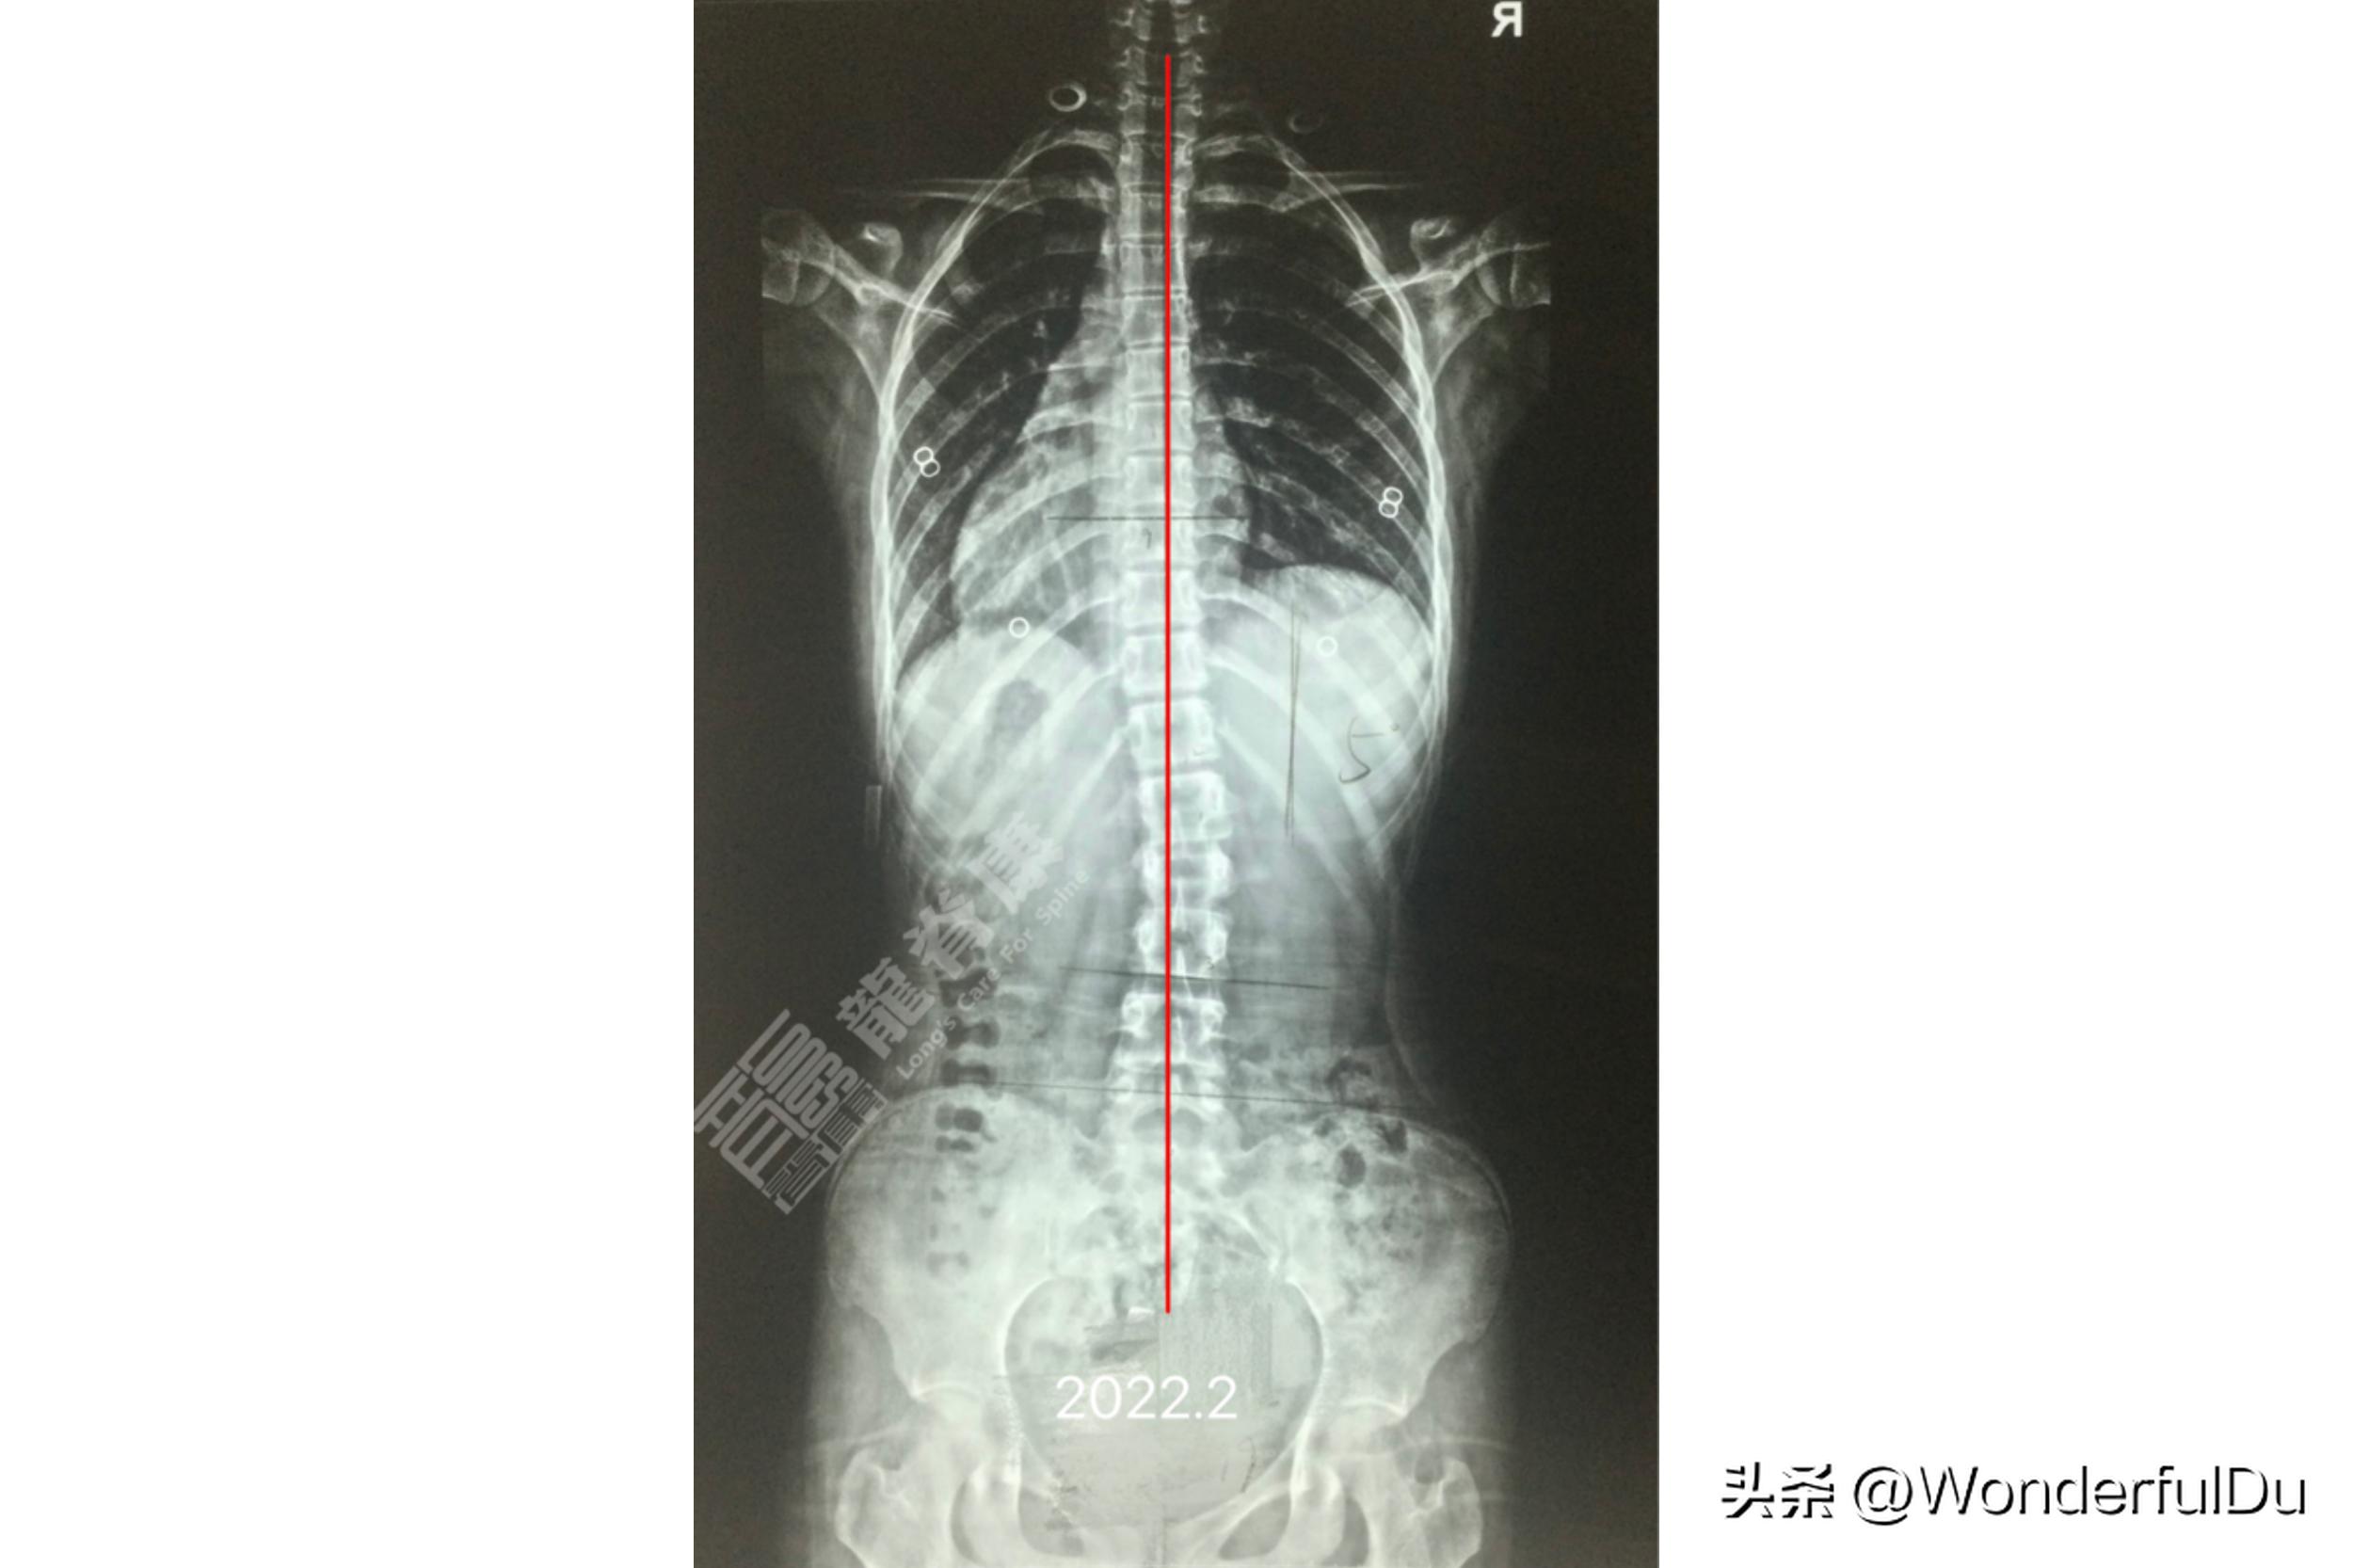

于是我们建议孩子进行7D疗法,定制鞋垫,进行施罗斯及运康锻炼。半年后拍片复查 侧弯角度从28°减为10° ,右侧胸腰交界 剃刀背从9°减为5° 。一直到现在连续3年复查,其侧弯度数及剃刀背 基本稳定 。

从x 光上可以看出小蓝 骨盆是不等高 的,其家长在2021.2.7去外院拍了全脊柱EOS成像(脱GBW支具 >12小时),提示:以T12-L1为中心向右侧凸,Cobb角约8°,胸腰交界向中线右偏移,Risser征:3-4级.